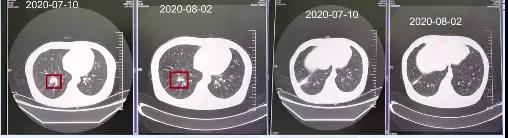

2020-08-02患者因需进行第二次化疗住院,检查发现患者各项肿瘤指标明显下降,肺部肿瘤组织明显缩小,体格检查较之前也有明显好转,疗效评估部分缓解(PR)。

2020-09-02患者因需进行第三次化疗住院。患者乏力症状虽然比治疗前好转,但是较第二次住院时并没有改善,同时头晕症状依旧明显。不过患者的神经系统还是有改善的,肿瘤相关指标也持续降低,胸部CT提示患者肿瘤组织进一步缩小,疗效评估PR。